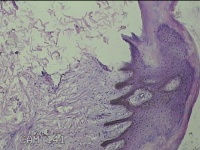

骶尾部包块

性别

男

年龄

37岁

临床诊断

骶良性肿瘤

一般病史

发现骶尾部包块10年余。

标本名称

大体所见

灰白粉红色组织3.5x1.3x1cm一块,表面带梭形皮肤3.5x1.3cm皮下见包块3x1.3cn一个,切开包块呈实性,切面灰白粉红色,质中。